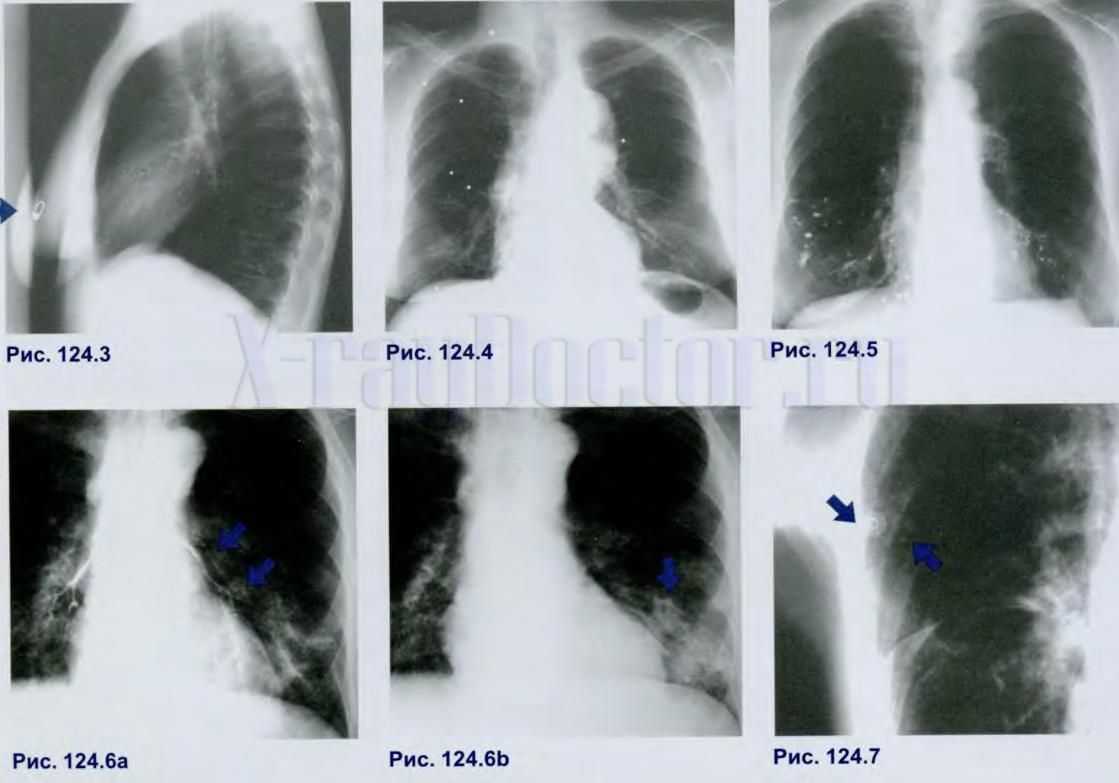

Рентгенограммы с белыми пятнами различного происхождения: 124.3 – пирсинг молочной железы, 124.4 – дробь в мягких тканях грудной клетки, 124.5 – профессиональный цементоз, 124.6а – контраст при бронхографии, 124.6b – пневмонический очаг, 124.7 – междолевой плеврит (стрелками обозначен артефакт)

Данный синдром является признаком множества патологических изменений в легких, но мы рассмотрим наиболее частые варианты.

При обнаружении пятен необходимо дополнительное исследование, позволяющее установить причину возникновения патологии. Для этих целей врач-рентгенолог может назначить рентгеновское обследование в дополнительных проекциях или выполнение послойной компьютерной или магнитно-резонансной томографии.